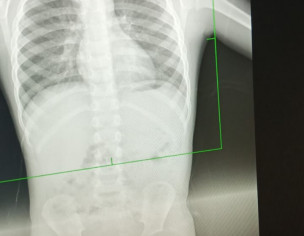

Asking for Other, Male, 4 years old, Okara

AOA Got this xray done for my son. He has cough and flu. Is it normal.